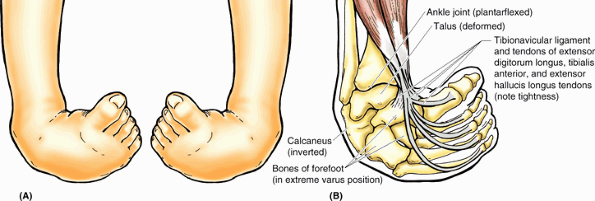

-

Gluteal region (L. regio glutealis).

This transitional region between the trunk and free lower limb includes

two parts of the lower limb: the rounded, prominent posterior region,

the buttocks (L. nates, clunes), and the lateral, usually less prominent hip (L. coxa) or hip region (L. regio coxae),

which overlies the hip joint and greater trochanter of the femur. Note

that the “width of the hips” in common terminology is a reference to

one’s transverse dimensions at the level of the greater trochanter. The

gluteal region is bounded superiorly by the iliac crest, medially by

the intergluteal (natal) cleft (L. natus, to be born), and inferiorly by the skin fold (groove) underlying the buttock, the gluteal fold (L. sulcus glutealis). The gluteal muscles constitute the bulk of this region. -